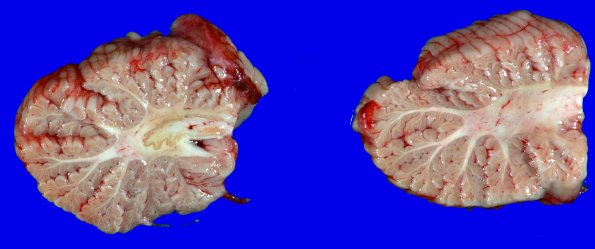

The cerebellum shows loss and discoloration of the white matter of the arbor vitae.